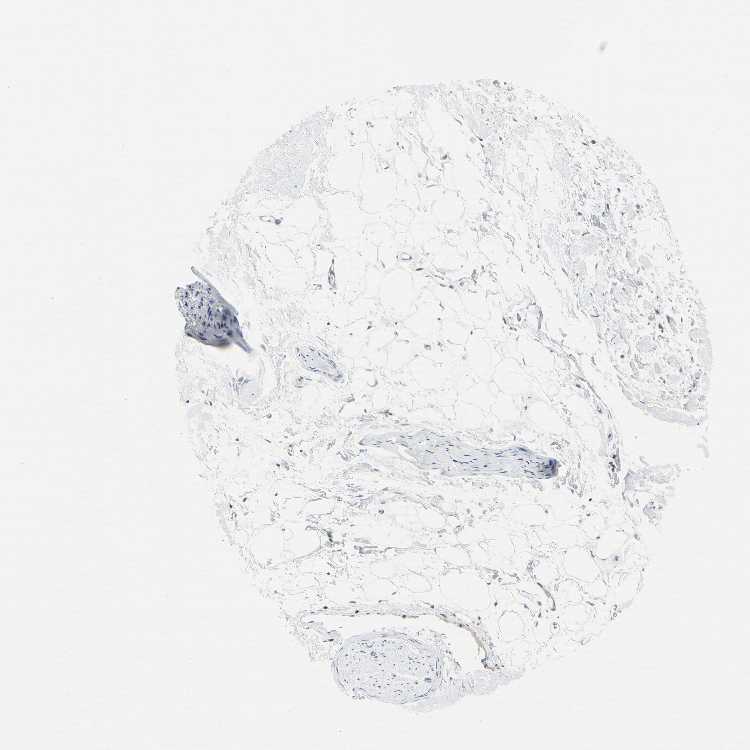

ADIPOSE TISSUE - Antibody stainingi

Antibody staining in the annotated cell types in the current human tissue is reported as not detected, low, medium, or high, based on conventional immunohistochemistry profiling in selected tissues. This score is based on the combination of the staining intensity and fraction of stained cells.

Each image is clickable and will lead to virtual microscopy that enables deeper exploration of all samples and also displays staining intensity scores, fraction scores and subcellular localization as well as patient and tissue information for each sample.

Antibody HPA008209Antibody HPA023483Antibody CAB034434

Adipocytes Not detectedNot detectedMedium